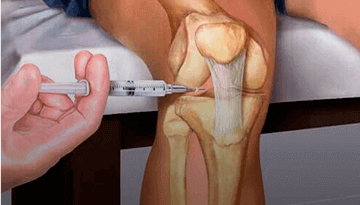

Боль и хруст в суставах, отеки и покраснения — это симптомы серьёзных проблем. Без своевременного лечения эти болезни становятся причиной полной потери подвижности и необратимой деформации суставов

«Заболевания опорно-двигательного аппарата – это всеобъемлющая проблема, с которой сталкивался практически каждый житель нашей Страны. Только остеоартрозом на сегодняшний день болеют 12% жителей Таджикистана независимо от возраста. Опасность таких болезней заключается в том, что они приводят к полной инвалидности. К счастью, несколько лет назад ведущими мировыми специалистами был разработан натуральный крем под названием Arteron. Как показала наша практика, применение крема Arteron позволяет избавиться от отечности, воспаления и боли в суставах и полностью восстановить их функции в домашних условиях всего за 2 недели...»

Курс использования Arteronа - 30 дней. Боль пройдет и к суставу (если он был обездвижен) начнут возвращаться функции уже через 7-10 дней.